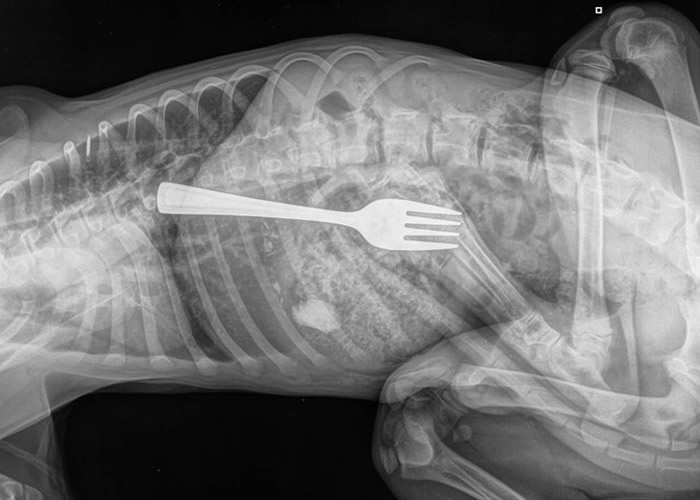

皮特夫妇表示,爱犬达斯廷(Dustin)当天跳上餐桌就大快朵颐。他们遍寻餐叉不果后,怀疑遭达斯廷吞掉,撬开狗嘴却一无所获。二人把它送往动物急救中心检查,果然在X光片中发现长约10厘米的餐叉。

兽医最终成功取出餐叉,亦对此感匪夷所思。至于皮特夫妇则松一口气,笑指其爱犬不知悔改,至今仍试图吞下看似能吃的东西。